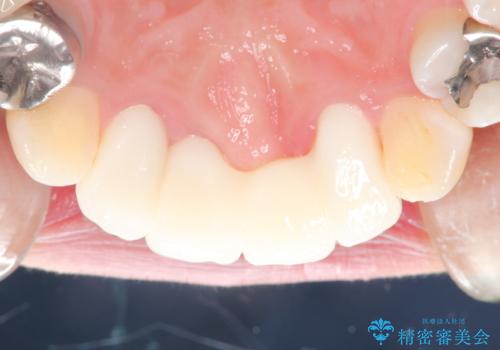

仮歯に変えた時点で臭いや色などが改善され、気に入っていただけました。

被せ物はなるべく白くしたいとの事で、ホワイトニングも行い綺麗に仕上がり、患者様は大変満足されました。